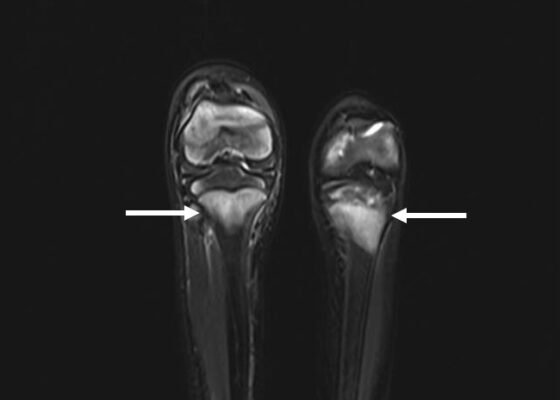

DOI: https://doi.org/10.21980/J89H1XHis lower extremity magnetic resonance imaging (MRI) findings showed abnormal signals in his knees, which were most consistent with scurvy. The white arrows on the T1-weight sequence indicate hypointensity (decreased signal or darker region) of the knees. The white arrows in the T2-weighted short-tau inversion recovery (STIR) sequence indicate hyperintensity (increased signal or brighter region) in an MRI of the knees.